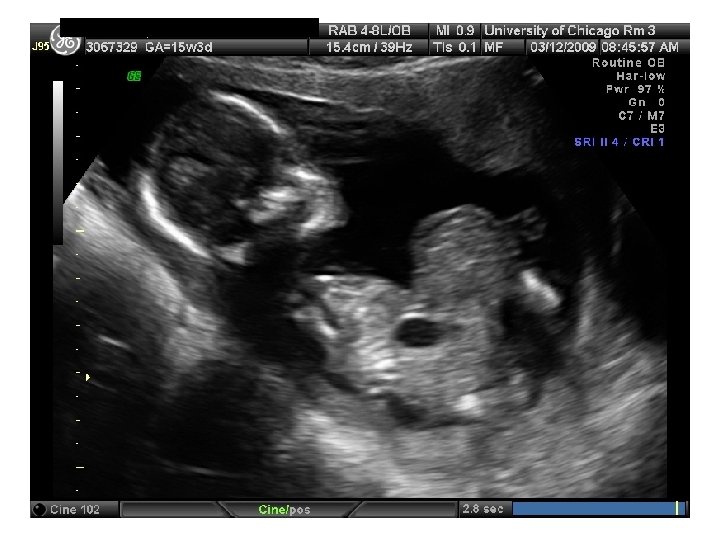

QUIZ What is Your Diagnosis? Case: Patient J. F. 30 years old, at 32 week gestation. Presented with the following pictures.

Answer: a) Trisomy 21 b) Non-immune Hydops c) Paravo virus Infection